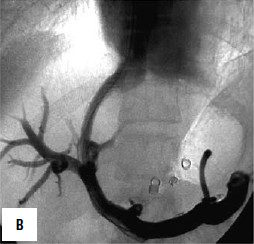

Дистальный спленоренальный анастомоз позволяет сохранить селезенку и не так резко снижает портальное давление, поскольку при этом кровь от воротной вены оттекает через сеть анастомозов и паренхиму селезенки. Такие хирургические вмешательства возможны при отсутствии симптомов печеночной недостаточности, грубых нарушений функционального состояния других органов. При функциональной ограниченности жизненно важных органов и систем целесообразно выполнить декомпрессию портальной системы с помощью чрезъяремного внутрипеченочного порто системного шунтирования (TIPS) (рис. 90). Операция осуществляется по следующей технологии: катетеризируют яремную вену, затем катетер проводят в верхнюю полую и потом в одну из печеночных вен. Далее катетер через ткань печени (перфорируя ее) проводят в одну из портальных вен. Баллонным катетером канал в печени между кавальной и портальной системами расширяют до 6–8 мм и стентируют специальным каркасомстентом.

Рис. 90. Операция чрезъяремного внутрипеченочного портосистемного шунтирования (TIPS): А – схема операции; Б – этап постановки стента; В – контроль проходимости стента